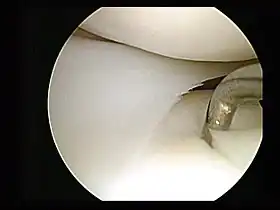

Arthroscopic surgery

Minimally invasive procedures were pioneered by interventional radiologists who had first introduced angioplasty and the catheter-delivered stent. Many other minimally invasive procedures have followed where images of all parts of the body can be obtained and used to direct interventional instruments by way of catheters (needles and fine tubes), so that many conditions once requiring open surgery can now be treated non-surgically.[2] A minimally invasive procedure typically involves the use of arthroscopic (for joints and the spine) or laparoscopic devices and remote-control manipulation of instruments with indirect observation of the surgical field through an endoscope or large scale display panel, and is carried out through the skin or through a body cavity or anatomical opening. Interventional radiology now offers many techniques that avoid the need for surgery.[2]

Many medical procedures are called minimally invasive; those that involve small incisions through which an endoscope is inserted, end in the suffix -oscopy, such as endoscopy, laparoscopy, arthroscopy. Other examples of minimally invasive procedures include the use of hypodermic injection, and air-pressure injection, subdermal implants, refractive surgery, percutaneous surgery, cryosurgery, microsurgery, keyhole surgery, endovascular surgery using interventional radiology (such as angioplasty or embolization), coronary catheterization, permanent placement of spinal and brain electrodes, stereotactic surgery, the Nuss procedure, radioactivity-based medical imaging methods, such as gamma camera, positron emission tomography and SPECT (single photon emission tomography). Related procedures are image-guided surgery, and robot-assisted surgery.[7]

Special medical equipment may be used, such as fiber optic cables, miniature video cameras and special surgical instruments handled via tubes inserted into the body through small openings in its surface. The images of the interior of the body are transmitted to an external video monitor and the surgeon has the possibility of making a diagnosis, visually identifying internal features and acting surgically on them.[8]